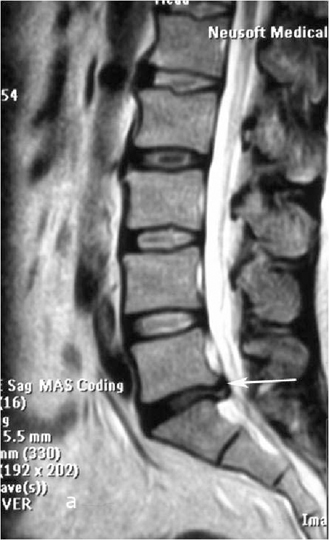

Больной К., 49 лет. Поступил в клинику с жалобами на боли в поясничном отделе позвоночника в течение многих лет. Последнее обострение отмечал около полугода, когда появились боли в левой ноге. Консервативная терапия у невролога без эффекта. При поступлении обращали на себя внимание корешковый синдром в левой ноге, болевой синдром в поясничном отделе позвоночника.

При рентгенографии (Рис.7) и МРТ (Рис.8) поясничного отдела позвоночника выявляется дегенеративный ретролистез L5 позвонка, секвестрированная  парамедианная грыжа мп диска L5-S1  слева.

Рис. 8a,b. Магнитно-резонансная томография (МРТ) поясничного отдела позвоночника в сагиттальной (a) и аксиальной (b) проекции. Стрелкой показана мп секвестрированная парамедианная грыжа диска L5-S1 слева.